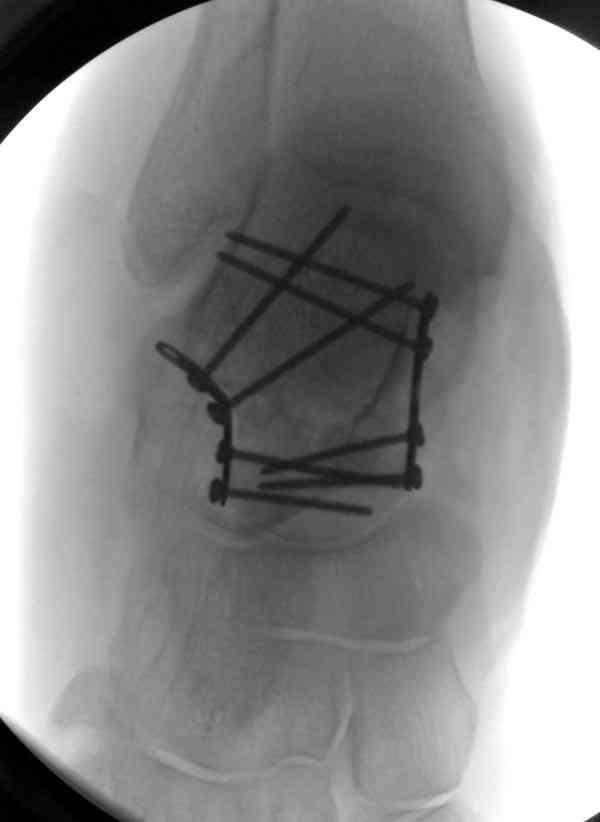

Случай с множественным оскольчатым переломом тарана оперированный из двойного доступа.

Через 14 мес.: